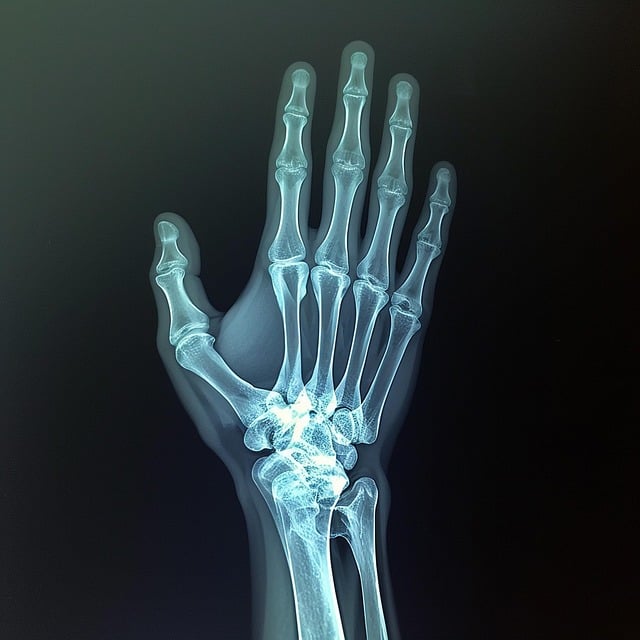

골관절염의 한 형태인 손 관절염은 손과 손가락의 관절이 퇴화되는 것이 특징인 질환입니다. 이 퇴화는 주로 연골의 점진적인 파괴, 즉 관절에 있는 뼈들 사이의 보호적인 완충 작용에서 비롯됩니다. 연골이 닳아 없어지면서 뼈들이 서로 비비기 시작하고, 이는 통증, 뻣뻣함, 관절 운동성의 상실로 이어집니다.

손 관절염에는 크게 골관절염과 류마티스관절염이 있습니다. 골관절염은 연골이 서서히 분해되는 과정을 동반하며 노화와 관련된 경우가 많습니다. 그런데 류마티스관절염은 자가면역질환으로 면역체계가 잘못해서 관절을 공격해 염증, 통증, 결국 관절 손상을 일으킵니다.

손 관절염이 진행됨에 따라, 관절이 눈에 띄게 부어오르고 손가락에 기형이 생길 수 있습니다. 마디 또는 뼈 성장은 손가락의 중간 또는 끝 관절에 형성되어, 그들의 외모를 바꾸고 불편함에 기여할 수 있습니다. 악력 또한 감소하여, 항아리를 열거나, 키를 돌리거나 셔츠 단추를 끼는 것과 같은 일상 활동에 영향을 미칠 수 있습니다.